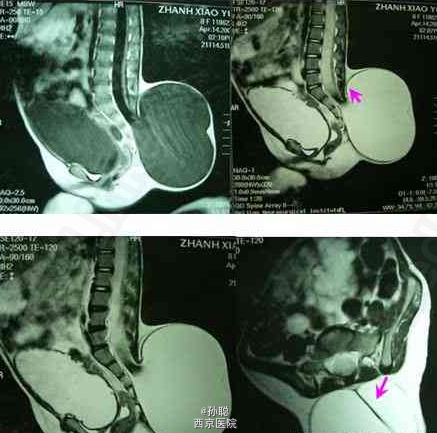

患者女性,9岁,发现腰臀后鼓包9年,伴二便失禁。查体:臀部上方囊性肿物,约27×25cm2大小,波动感,透光实验阳性,肛门外口有残留粪便,肛门括约肌松弛,鞍区针刺痛觉减退,耻骨上叩诊浊音。B超:膀胱残余尿量约500ml。术前影像学资料显示:腰骶管脊柱裂,脊髓、神经根和脊膜膨出,内容为脑脊液,脊髓圆锥低位,脊髓拴系形成。 手术将突出于椎管外的脊髓和神经样结构还纳,终丝切断、拴系松解,膨出的硬脊膜翻转缝合,在椎管内水平重建硬脊膜腔,逐层翻转、加固缝合,皮肤塑性缝合。术后影像学资料显示:完整的、椎管内水平的硬膜结构。